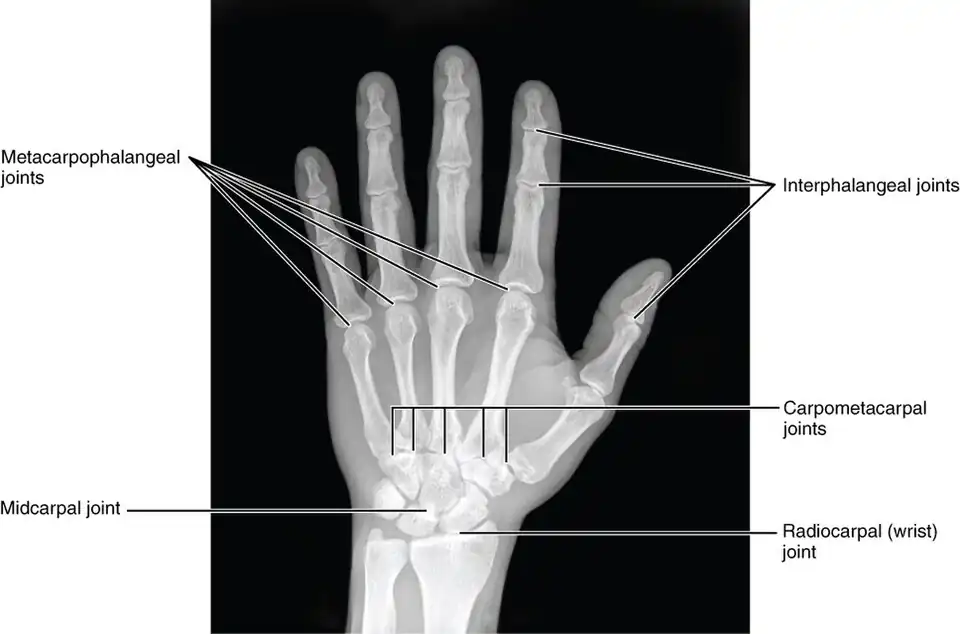

A phalanx is named according to whether it is proximal, middle, or distal and its associated finger or toe. The proximal phalanges are those that are closest to the hand or foot. In the hand, the prominent, knobby ends of the phalanges are known as knuckles. The proximal phalanges join with the metacarpals of the hand or metatarsals of the foot at the metacarpophalangeal joint or metatarsophalangeal joint. The intermediate phalanx is not only intermediate in location, but usually also in size. The thumb and large toe do not possess a middle phalanx. The distal phalanges are the bones at the tips of the fingers or toes. The proximal, intermediate, and distal phalanges articulate with one another through interphalangeal joints of hand and interphalangeal joints of the foot.[4]: 708–711 : 708–711